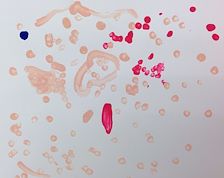

Comment on Lincoln2518's Artwork

View Lincoln2518's portfolio